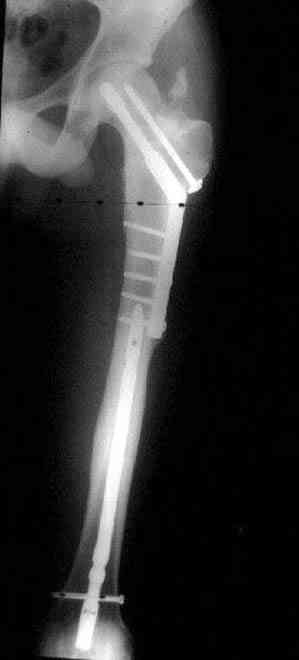

Уважаемые коллеги. Благодарим за дискуссию. Мы решили выполнить комбинированную операцию - эндопротезирование тазобедренного сустава и ретроградный интрамедуллярный остеосинтез (одномоментно)

Наверно, вариант с вальгизирующей остеотомией с фиксацией blade plate или DHS более щадящий. А диафиз можно рефиксировать ретроградно. Или про эндопротезирование с очень длинной ножкой подумать.

Или при наличии ретроградной техники, короткий штифт с одним блокирующим шурупом дистально, создаст адекватную фиксацию и условия для быстрейшего восстановления.